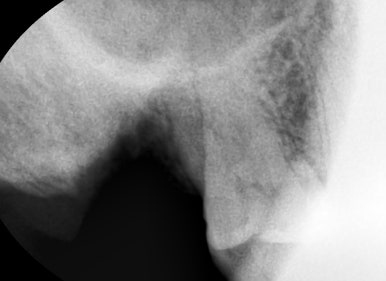

치아가 파절되어 두동강난 모습

신경치료를 하고 크라운을 하지 않고 몇년간 방치하여 부러진 치아